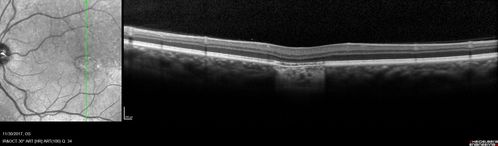

Torpedo Maculopathy

Likely a variant of CHRPE